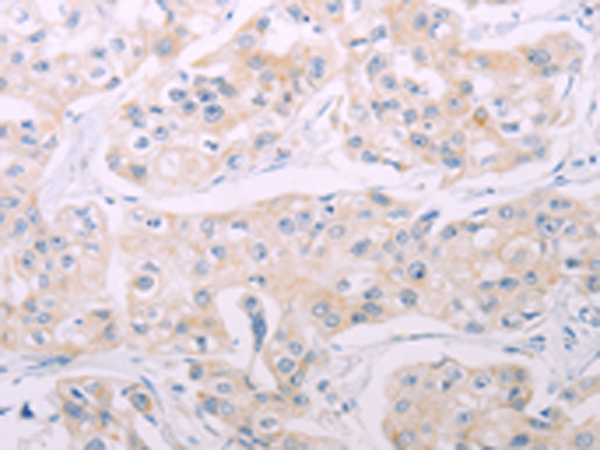

分类: 科研抗体货号: P04545别名: AC7应用: IHC反应种属: Human